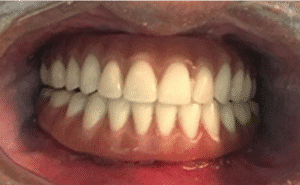

Reabilitação de maxilas atróficas com implantes zigomáticos: relato de caso clínico 02

Paciente de 48 anos, do sexo feminino, apresentando boa saúde geral, procurou atendimento odontológico para reabilitação maxilar. A mesma relatou